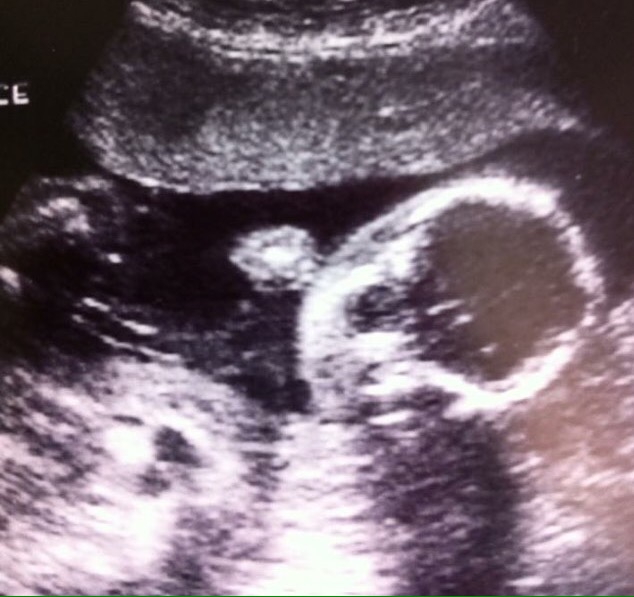

For many of you, I feel like this is a “well, duh” moment. For me… well… the idea of such an occurrence never crossed my mind. I had always assumed that if something were “off” with the baby, our prenatal ultrasound at 20 weeks would have shown it. This is a small part of the reason that those first several hours after her birth were so rattling for me – I couldn’t understand how no one had any idea of this prior to birth.

Looking back on that silly, smushy face on the ultrasound machine, I am even more amused at the surprises she had in store for us. Being a girl, coming early, being a blonde, having Down syndrome… take your pick. That birth day was anything but ordinary.